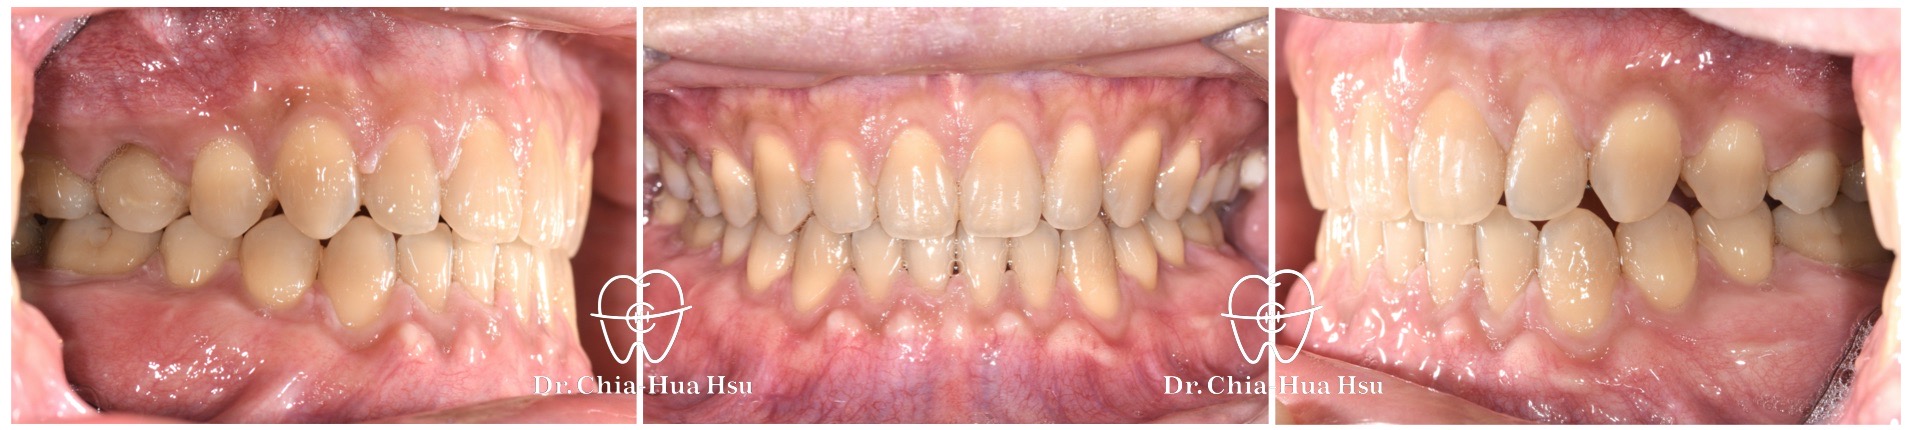

• 治療方式:使用傳統金屬矯正器,配合下顎頰側迷你骨釘拉動牙齒 ; 右上第二乳臼齒因為骨沾黏無法移動,故以樹脂修復、恢復咬合功能。

• 治療時間:2 年。

• 治療結果:齒列排齊、縫隙關閉,咬合功能也改善許多。

治療前

治療後